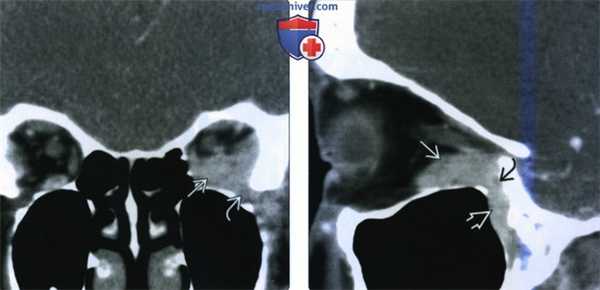

(Слева) При КТ с КУ в корональной проекции в нижней части левой глазницы определяется инфильтративное лимфопролиферативное образование, прорастающее в нижнюю глазничную щель. Отмечаются типичные гомогенность и нечеткость контуров новообразования.

(Справа) При КТ с КУ в сагиттальной проекции наблюдается дальнейшее инфильтративное распространение опухоли из задней части глазницы через нижнюю глазничную щель в крылонебную ямку. Нечетко отграниченные новообразования зачастую принадлежат к более агрессивному гистологическому типу.